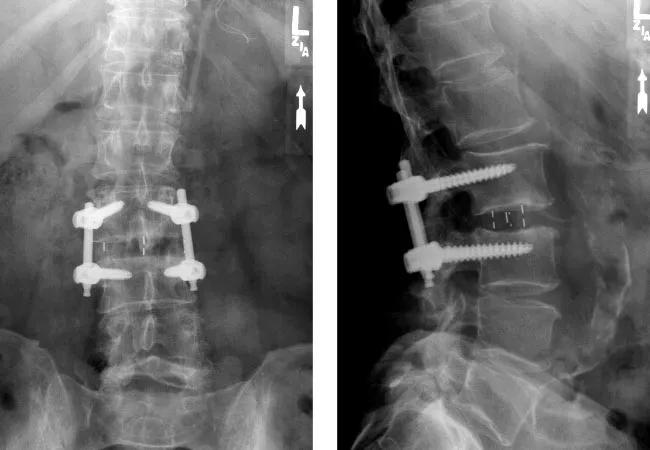

15-NEU-2536-Patient-B

Patient B is a 38-year-old male with a history of back pain due to thoracolumbar kyphoscoliosis. Intraoperative X-rays show the extent of correction that can be achieved using LLIF technique through a single 2 cm incision. The second posterior stage was performed the same day. Bottom two images are from two years postsurgery — three months after the patient received his second-degree black belt in taekwondo.